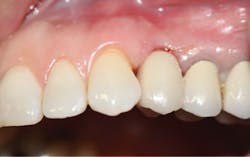

A 50-year-old female presented with a missing tooth No. 12 that was extracted for unknown reasons more than 10 years ago (figure 7). The patient was referred to our office for an implant consultation. Upon review of a CT scan, it was revealed that at the widest area buccal-lingually there was 4.09 mm and at the narrowest 3.8 mm (figure 8). She was presented with two treatment options: bone grafting or a narrow-diameter implant. She opted for the narrow-diameter implant, as it eased several of her concerns: she was unhappy with a removable appliance, worried about a block graft for a single tooth, and finances were a burden.

A 1.8 mm x 14 mm Anew implant (Dentatus) was selected, and a surgical guide was fabricated for a flapless approach. In this instance, a healing cap was placed, and the existing flipper was relieved to address financial concerns (figures 9 and 10). A screw-retained crown was fabricated three months post insertion (figures 11 and 12). The patient reported no postoperative discomfort, and the case remains successful, as shown in the two-year postoperative x-ray (figure 13).

Figure 10: Implant exposed for impression

Figure 12: Final crown seating